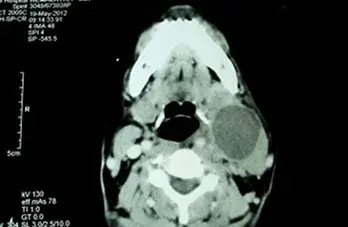

Barium Swallow

Bleeding Polypus Nose

Chicken Bone Nasopharynx

Conductive HL Audiogram

Endoscopic Ear Visualisation

Large Central Perforation

Mastoidectomy

Oropharyngeal Rhinosporidiosis

Tonsillitis

Fb Cricopharynx

Haller Cell

Inverted Papilloma Nose

Mastoidectomy 2

Mastoidectomy Cavity

Nasal Rhinosporidiosis

Neck Abscess

Palatal Ulcer

Retropharyngeal Abscess